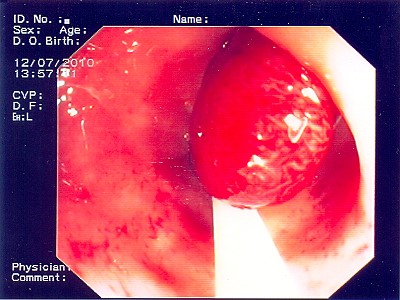

Wie bei den Abbildungen 28 und 30 handelt es sich um einen breitbasigen, relativ flachen, noch nicht entarteten Polyp, der sich mit einer Schlinge nicht vollständig abtragen ließe.